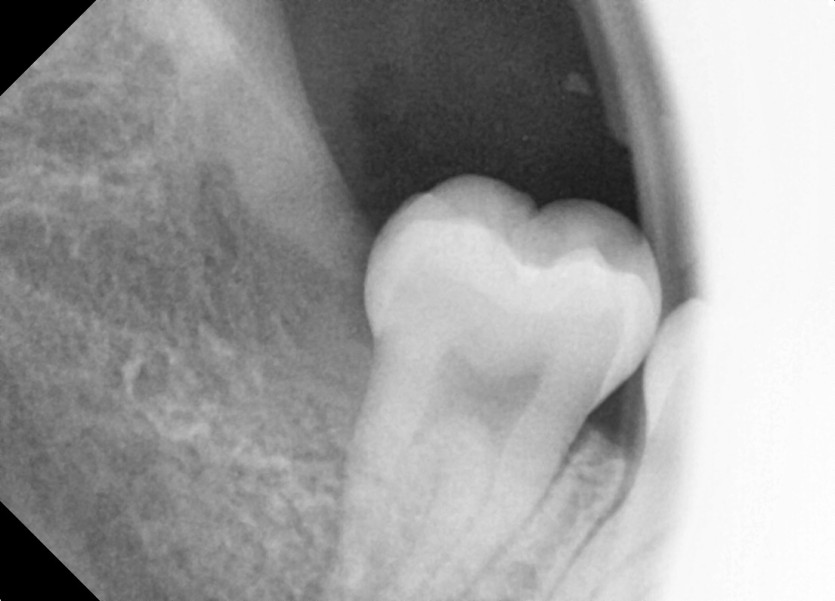

#18,28,38,48 사랑니 발치

구강 외과 전문의가 당일 발치했습니다.